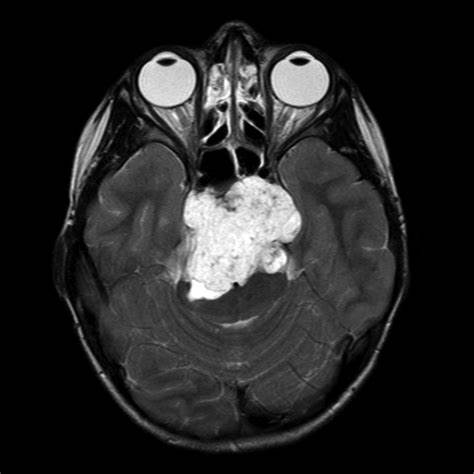

【脊索瘤案例】年仅22岁的95后小姑娘雯雯(化名)怎么也没想到,自己持续3个月的头痛、头晕、耳鸣一经检查就是“桥前斜坡脊索瘤”,颅内比较少见的一种...

相信在生活中,都基本出现过头痛、头晕、耳鸣这些生活中比较常见的症状,但是年仅22岁的95后小姑娘雯雯(化名)却因头痛、头晕、耳鸣被查出桥前斜坡脊...